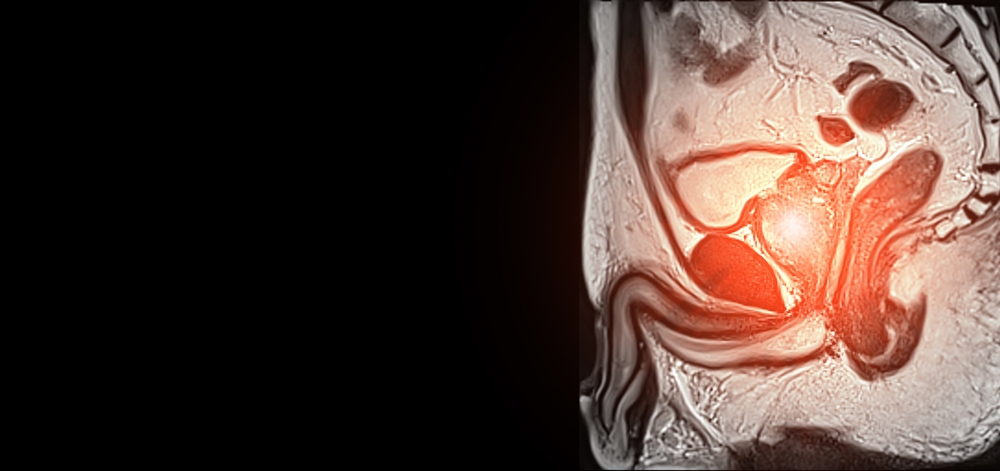

- Varpa: Tai raumeninis vamzdelio formos organas, kuris seksualinio sujaudinimo metu prisipildo kraujo ir tampa standus, todėl galimi lytiniai santykiai.

- Kapšelis: Tai odinis maišelis, esantis po varpa, kuris saugo ir palaiko tinkamą temperatūrą sėklidėms.

- Sėklidės: Dvi ovalios formos liaukos, kuriose subręsta spermatozoidai bei gaminasi testosteronas.